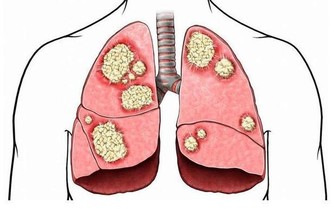

3. 鞏膜發黃:肝炎

鞏膜發黃是臨床上診斷肝病的重要依據,甲肝、急性乙肝患者大多都有不同程度的鞏膜發黃症狀。